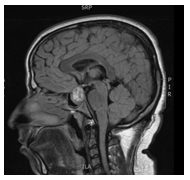

A 31years old man presented to the emergency department with five days history of severe headache accompanied by nausea, dizziness, and blurred vision. The patient’s past medical history was unremarkable and was not on any medications. He is married with 3children, the youngest is 3years old. On physical exam, he was hemodynamically stable with no orthostasis, conscious, oriented and in moderate pain distress (5/10 on pain scale chart). His central nervous system exam showed normal mini-mental status, cranial nerves examination was normal with preserved visual fields. His presentation prompted a brain MRI which showed pituitary macroadenoma with a suprasellar extension (Figure 1) with hemorrhage suggestive of pituitary apoplexy. Hormonal profiles is shown in Table 1, consistent with panhypopituitarism due to non-functional pituitary macro-adenoma with apoplexy. The decision for conservative management was opted for in keeping with the severity of the presentation. He improved and discharged 2days later on hydrocortisone and levothyroxine. However, a few days later he expressed a major concern of diminished libido and sexual dysfunction. At this point, Cabergoline 0.5mg orally twice weekly (off-label) was started with an improvement in his sexual functions within a few days, recovering his pituitary functions (off hormonal replacement). Follow-up MRIs (Figure 2) showed marked shrinkage of the macroadenoma which completely resolved in the most recent image (Figure 3) two years later.

Figure 2 Marked shrinkage of the macroadenoma